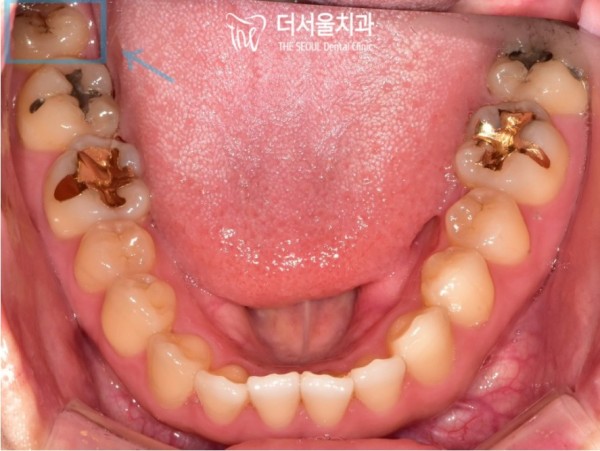

한눈에 보다오 사랑니의 교합면 중심구에 충치가 보입니다.

검게 퍼져있는 충치가 잘 보이죠? 사랑니가 올곧게 자라나 있지만

너무 깊은곳에 있는 사랑니는 양치질이 잘 되지 않아서

이렇게 충치가 생기기 쉽습니다.

이러한 이유로, 올곧게 자란 사랑니도 발치를 하게된답니다.

At a glance, you can see a cavity in the center of the occlusal surface of the wisdom tooth.

You can see the black tooth, right? My wisdom tooth is growing straight

Wisdom teeth that are too deep can't be brushed well

It's easy to get cavities like this.

For this reason, straight wisdom teeth are also pulled out.